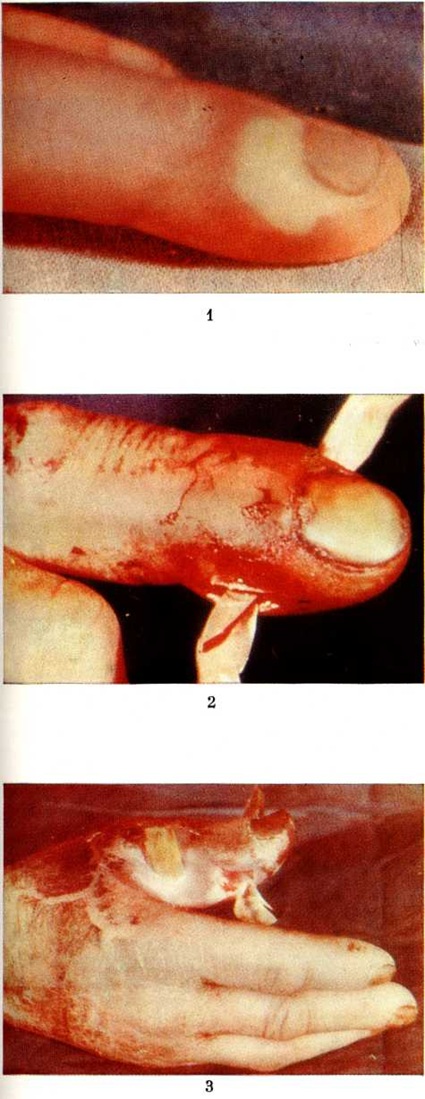

ПанарицийПанариций (латынь panaricium) острое воспаление тканей пальца, возникающее обычно в результате инфицирования мелких его повреждений. Воспалительные процессы, осложняющие обширные ранения пальцев, не относятся к Панариций В этих случали говорят об инфицированных ранах пальцев. Классификация. Для практической работы хирургов наиболее целесообразна классификация Панариций, основанная на учёте анатомической локализации воспалительного процесса (рисунок 1). По этой классификации различают следующие виды Панариций: кожный, околоногтевой (паронихия), подногтевой, подкожный, костный, суставной, сухожильный, пандактилит. Статистика. Чаще Панариций болеют лица, выполняющие работу, связанную с возможностью травмирования рук, загрязнением их смазочными материалами, раздражающими кожу веществами (разнорабочие, грузчики, слесари, трактористы, рабочие ткацкой промышленности и другие). У 80% заболевших наблюдается Панариций ногтевых фаланг I, II или III пальцев правой кисти. Этиология и патогенез. Наиболее распространённым возбудителем Панариций является белый или золотистый гемолитический стафилококк в монокультуре или в ассоциации с другими микробами. Реже воспаление обусловливается кишечной палочкой, протеем, стрептококком и другие. Иногда причиной заболевания служит гнилостная, а также грибковая инфекция. Микробы проникают в ткани из окружающей среды или поверхностных слоёв кожи пальца при мелких, особенно не санированных повреждениях (ссадины, раны, нанесённые острыми предметами иголками, металлическими стружками, деревянными занозами и другие); крайне редко инфицирование происходит гематогенным путём. Возникновению Панариций способствуют снижение иммунологический реактивности организма, истощение, нарушение обмена веществ, эндокринные заболевания, а также длительное воздействие на кожу рук раздражающих веществ, холода, влаги, вибрации, при которых наступают расстройства микроциркуляции и трофики тканей, нарушается защитная функция кожи. Экспериментально доказано, что многие химический вещества и металлы (медь, цинк, кобальт, хром и другие), попадая в рану, оказывают на ткани токсическое действие и также способствуют возникновению Панариций Дальнейшее развитие и особенности течения Панариций в отличие от гнойных заболеваний других локализаций в значительной мере определяются особенностями анатомического строения пальца: обилием на небольшом протяжении функционально важных образований (фиброзные влагалища, сухожилия, синовиальные влагалища, сосуды, элементы, образующие суставы), ячеистостью расположения подкожной клетчатки, пронизанной фиброзными перемычками. Все эти факторы способствуют проникновению инфекции вглубь и переходу её на сухожилия и костносуставной аппарат. Фаза серозного пропитывания тканей обычно короткая, быстро сменяется фазой гнойно-некротического воспаления, так как скопление экссудата в замкнутых пространствах приводит в короткие сроки к нарушению кровообращения, некрозу тканей, гнойному их расплавлению. Клиническая картина. Постоянным признаком всех форм Панариций является сильная боль пульсирующего характера, резче выраженная в центре гнойного очага и при локализации его на ладонной поверхности пальца, где ткани неподатливы и обильно снабжены нервными окончаниями. Боль усиливается при движениях пальца, находящегося обычно в полусогнутом положении. Как правило, имеются выраженные в разной мере припухлость и отёчность пальца, гиперемия кожи, наиболее чётко определяющиеся на тыльной его поверхности, местное повышение температуры. Общие нарушения в организме больных выражены меньше, чем местные. В стадии нагноения боль становится мучительной, приводит к бессоннице; яркая краснота отмечается больше на периферии очага, чем в центре; температура тела повышена (с ремиссиями); определяются увеличение и болезненность регионарных лимфатических, узлов. При кожном Панариций гнойный очаг располагается в толще кожи (рис.< 1, 1) под эпидермисом. Образуется импетигиозный пузырь с серозным, гнойным или геморрагическим содержимым, который может располагаться как на ладонной, так и на тыльной поверхности любой из фаланг, иногда занимая почти всю поверхность пальца. |

Пузырь окружён узким воспалительным валиком. Боль вначале незначительная, но по мере накопления гноя усиливается, становится постоянной, пульсирующей. Иногда очаг гиперемии вокруг пузыря расширяется, присоединяется лимфангиит (смотри полный свод знаний) и регионарный лимфаденит (смотри полный свод знаний), сопровождающийся повышением температуры тела до высоких цифр. Ранее подобное поражение называли лимфатическим панарицием. В современной хирургической литературе этот термин практически не употребляется. При кожном Панариций гнойный очаг в толще кожи может сообщаться с очагом в подкожной клетчатке — так называемый панариций в форме запонки (рисунок 1, 8).

При околоногтевом Панариций— паронихии (смотри полный свод знаний) гнойное воспаление локализуется в толще валика ногтя: в боковом его участке, над корнем ногтя, или на всем протяжении валика (рисунок 1, 2). Кожа валика краснеет, припухает (цветной рисунок 1), из-под валика при надавливании появляются капли гноя.

Подногтевой Панариций характеризуется скоплением гноя под телом ногтя (рисунок 1,5). Он возникает при инфицировании проникающих под ноготь колотых ран, нагноении подногтевых гематом или как осложнение паронихии; протекает остро. Ноготь приподнят, сквозь него просвечивает гной. Ограничение гнойного очага плотной ногтевой пластинкой обусловливает постоянную резко выраженную пульсирующую боль.

Подкожный Панариций— воспаление подкожной клетчатки пальца (рисунок 1, 4) — наиболее распространённая форма Панариций Чаще встречается подкожный Панариций ладонной поверхности дистальных фаланг. Так как на тыльной поверхности пальцев кожа подвижная, а подкожная клетчатка рыхлая и содержит много лимфатических, сосудов, широко анастомозирующих с лимфатических, сосудами ладонной поверхности, то при расположении гнойного очага на ладонной поверхности пальца отёк, припухлость и гиперемия кожи более чётко выражены на боковых поверхностях и тыле пальца. Палец (или фаланга) увеличивается в объёме, становится напряжённым (цветной рисунок 2, 3). Большая толщина, плотность и неподатливость кожи ладонной поверхности, ячеистое расположение подкожной клетчатки способствуют быстрому распространению воспалительного процесса в сторону надкостницы и сухожилий. Боль постоянная, усиливается при разгибании и ослабевает при умеренном сгибании пальца. Точка наибольшей болезненности соответствует локализации центра гнойного очага. Часто больной лишается сна из-за боли, изнурён, температура тела повышается до 38—39°. В гнойное воспаление могут вовлекаться кость, сухожилия, суставы (рисунок 2). Из очага, локализующегося в проксимальной фаланге пальца, гнойный процесс может перейти по рыхлой клетчатке межпальцевых промежутков в каналы червеобразных мышц, дистальный отдел ладони и на проксимальные фаланги соседних пальцев (рисунок 3).